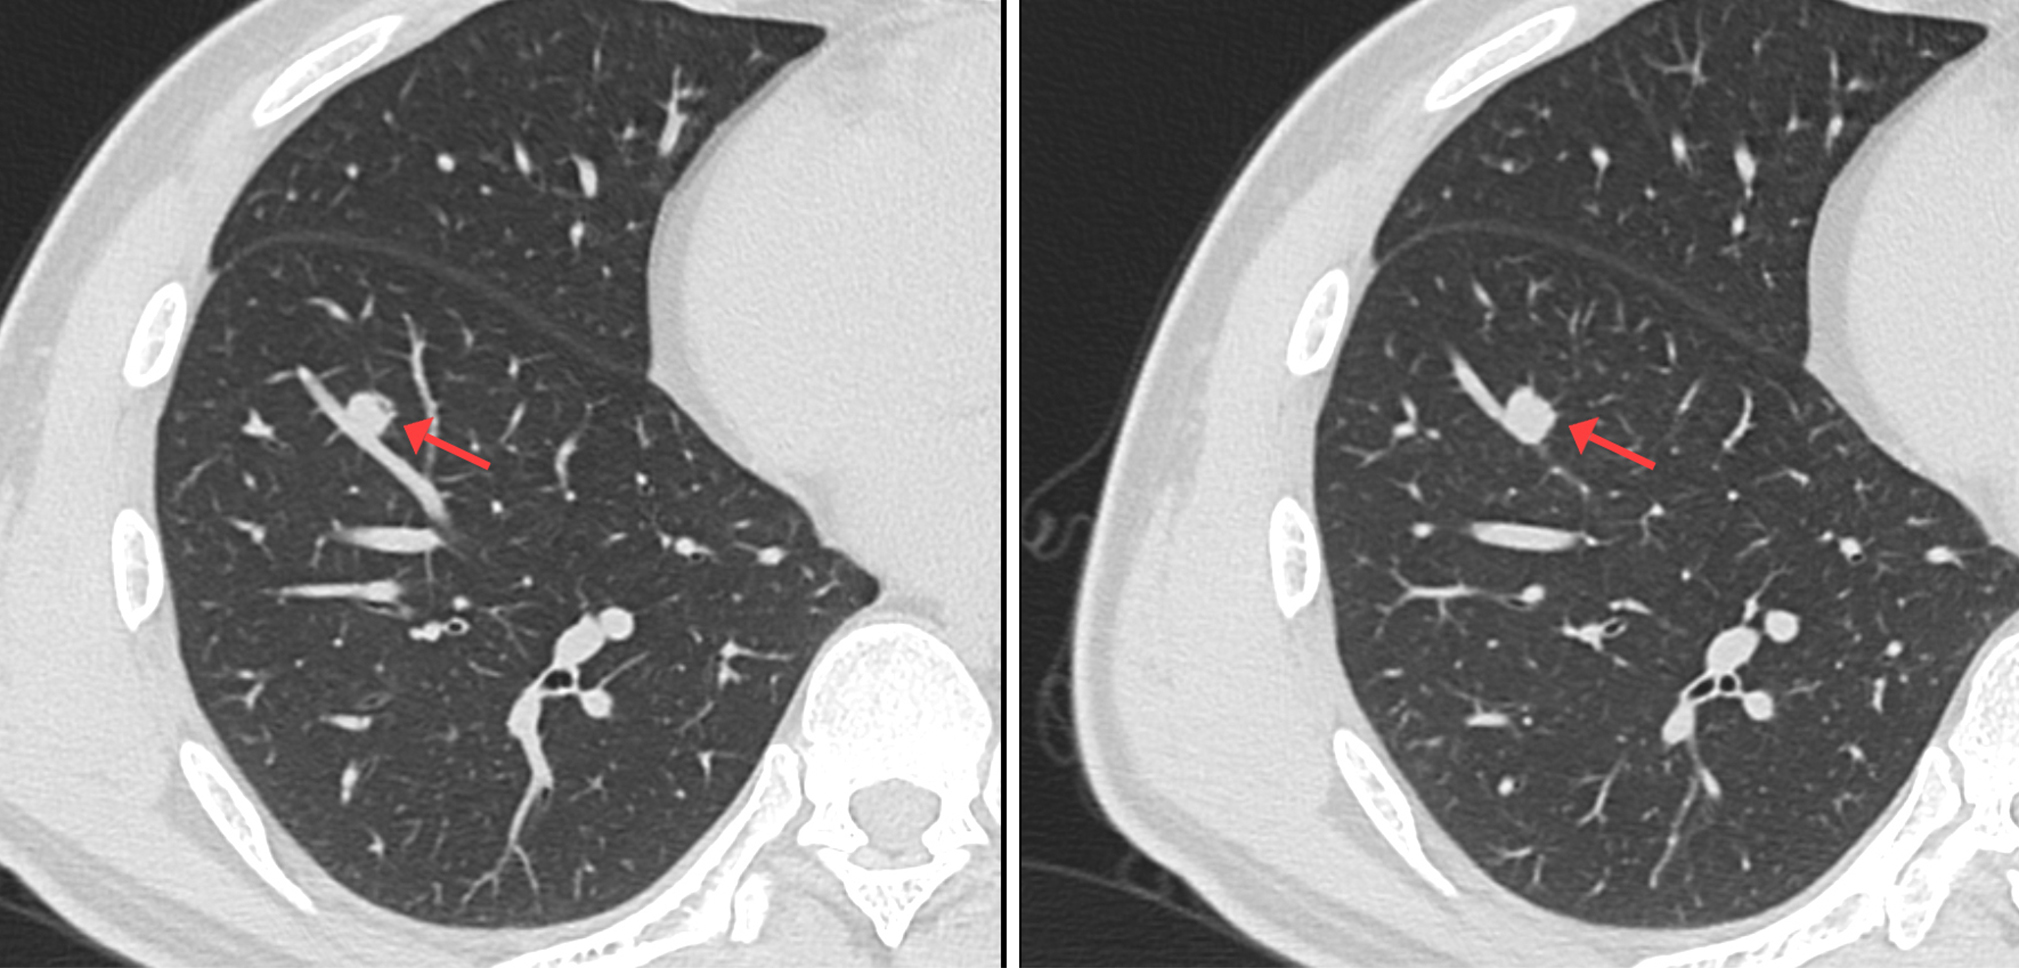

CT影像圖

靶掃描影像圖

靶掃描示:右肺下葉實(shí)性結(jié)節(jié),考慮腫瘤性病變可能性大,建議PET-CT進(jìn)一步檢查。2、左肺上葉尖后段磨玻璃結(jié)節(jié)及右肺上葉淡薄小片絮影,建議短期隨診復(fù)查。